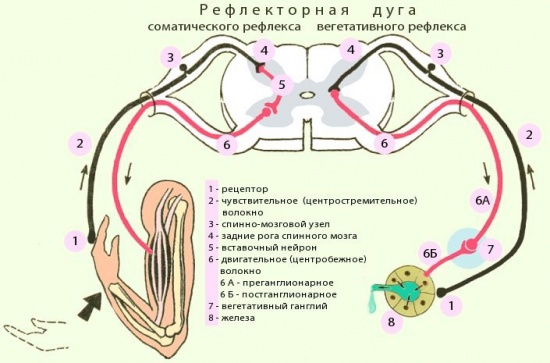

Рефлекторная дуга – это путь, который при осуществлении рефлекса, проходимый нервными импульсами.

Состоит рефлекторная дуга из:

рецептора – это нервное звено, которое воспринимает раздражение;

афферентного звена – это нервное центростремительное волокно - это отростки рецепторных нейронов, которые осуществляют передачу импульсов в центральную нервную систему от чувствительных нервных окончаний;

центрального звена – это нервный центр (необязательный элемент, к примеру, для аксон-рефлекса);

эфферентного звена, который осуществляет передачу к эффектору от нервного центра;

эффектора – это исполнительный орган, деятельность которого меняется в результате рефлекса.

На рисунке мы можем подробнее рассмотреть схему рефлекторной дуги.

Рис. 4 Схема рефлекторной дуги.